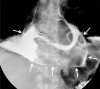

An esophagopericardial fistula is a rare complication of esophageal malignancy, trauma, or surgery. Imaging is a cornerstone of diagnosis, with detection of pneumopericardium or hydropneumopericardium at imaging raising suspicion for pyopneumopericardium and prompting immediate search for the causative pathologic process. Given the high associated mortality rate of over 50% for patients with esophagopericardial fistulas, early diagnosis and intervention are vital. Supplemental material is available for this article. © RSNA, 2020.